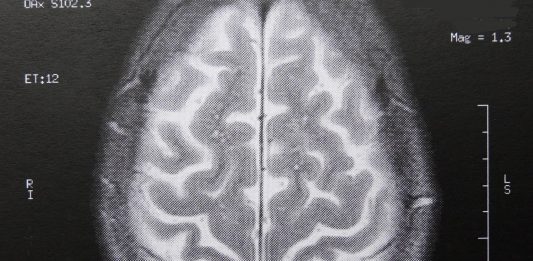

BERLIN. Wissenschaftler der Berliner Charité haben nachgewiesen, dass sich Änderungen am Bauplan eines bestimmten Gens die Leistungen in Intelligenztests verschlechtern. Demnach haben Umweltfaktoren über sogenannte epigenetische Veränderungen des Erbguts mehr Einfluss auf die Intelligenz als bisher angenommen wurde. Umwelteinflüsse, zum Beispiel Stress und belastende Erfahrungen, können die Aktivität von Genen beeinflussen und zu individuellen Strukturveränderungen … Genforscher: Stress mindert die Intelligenz – dauerhaft weiterlesen